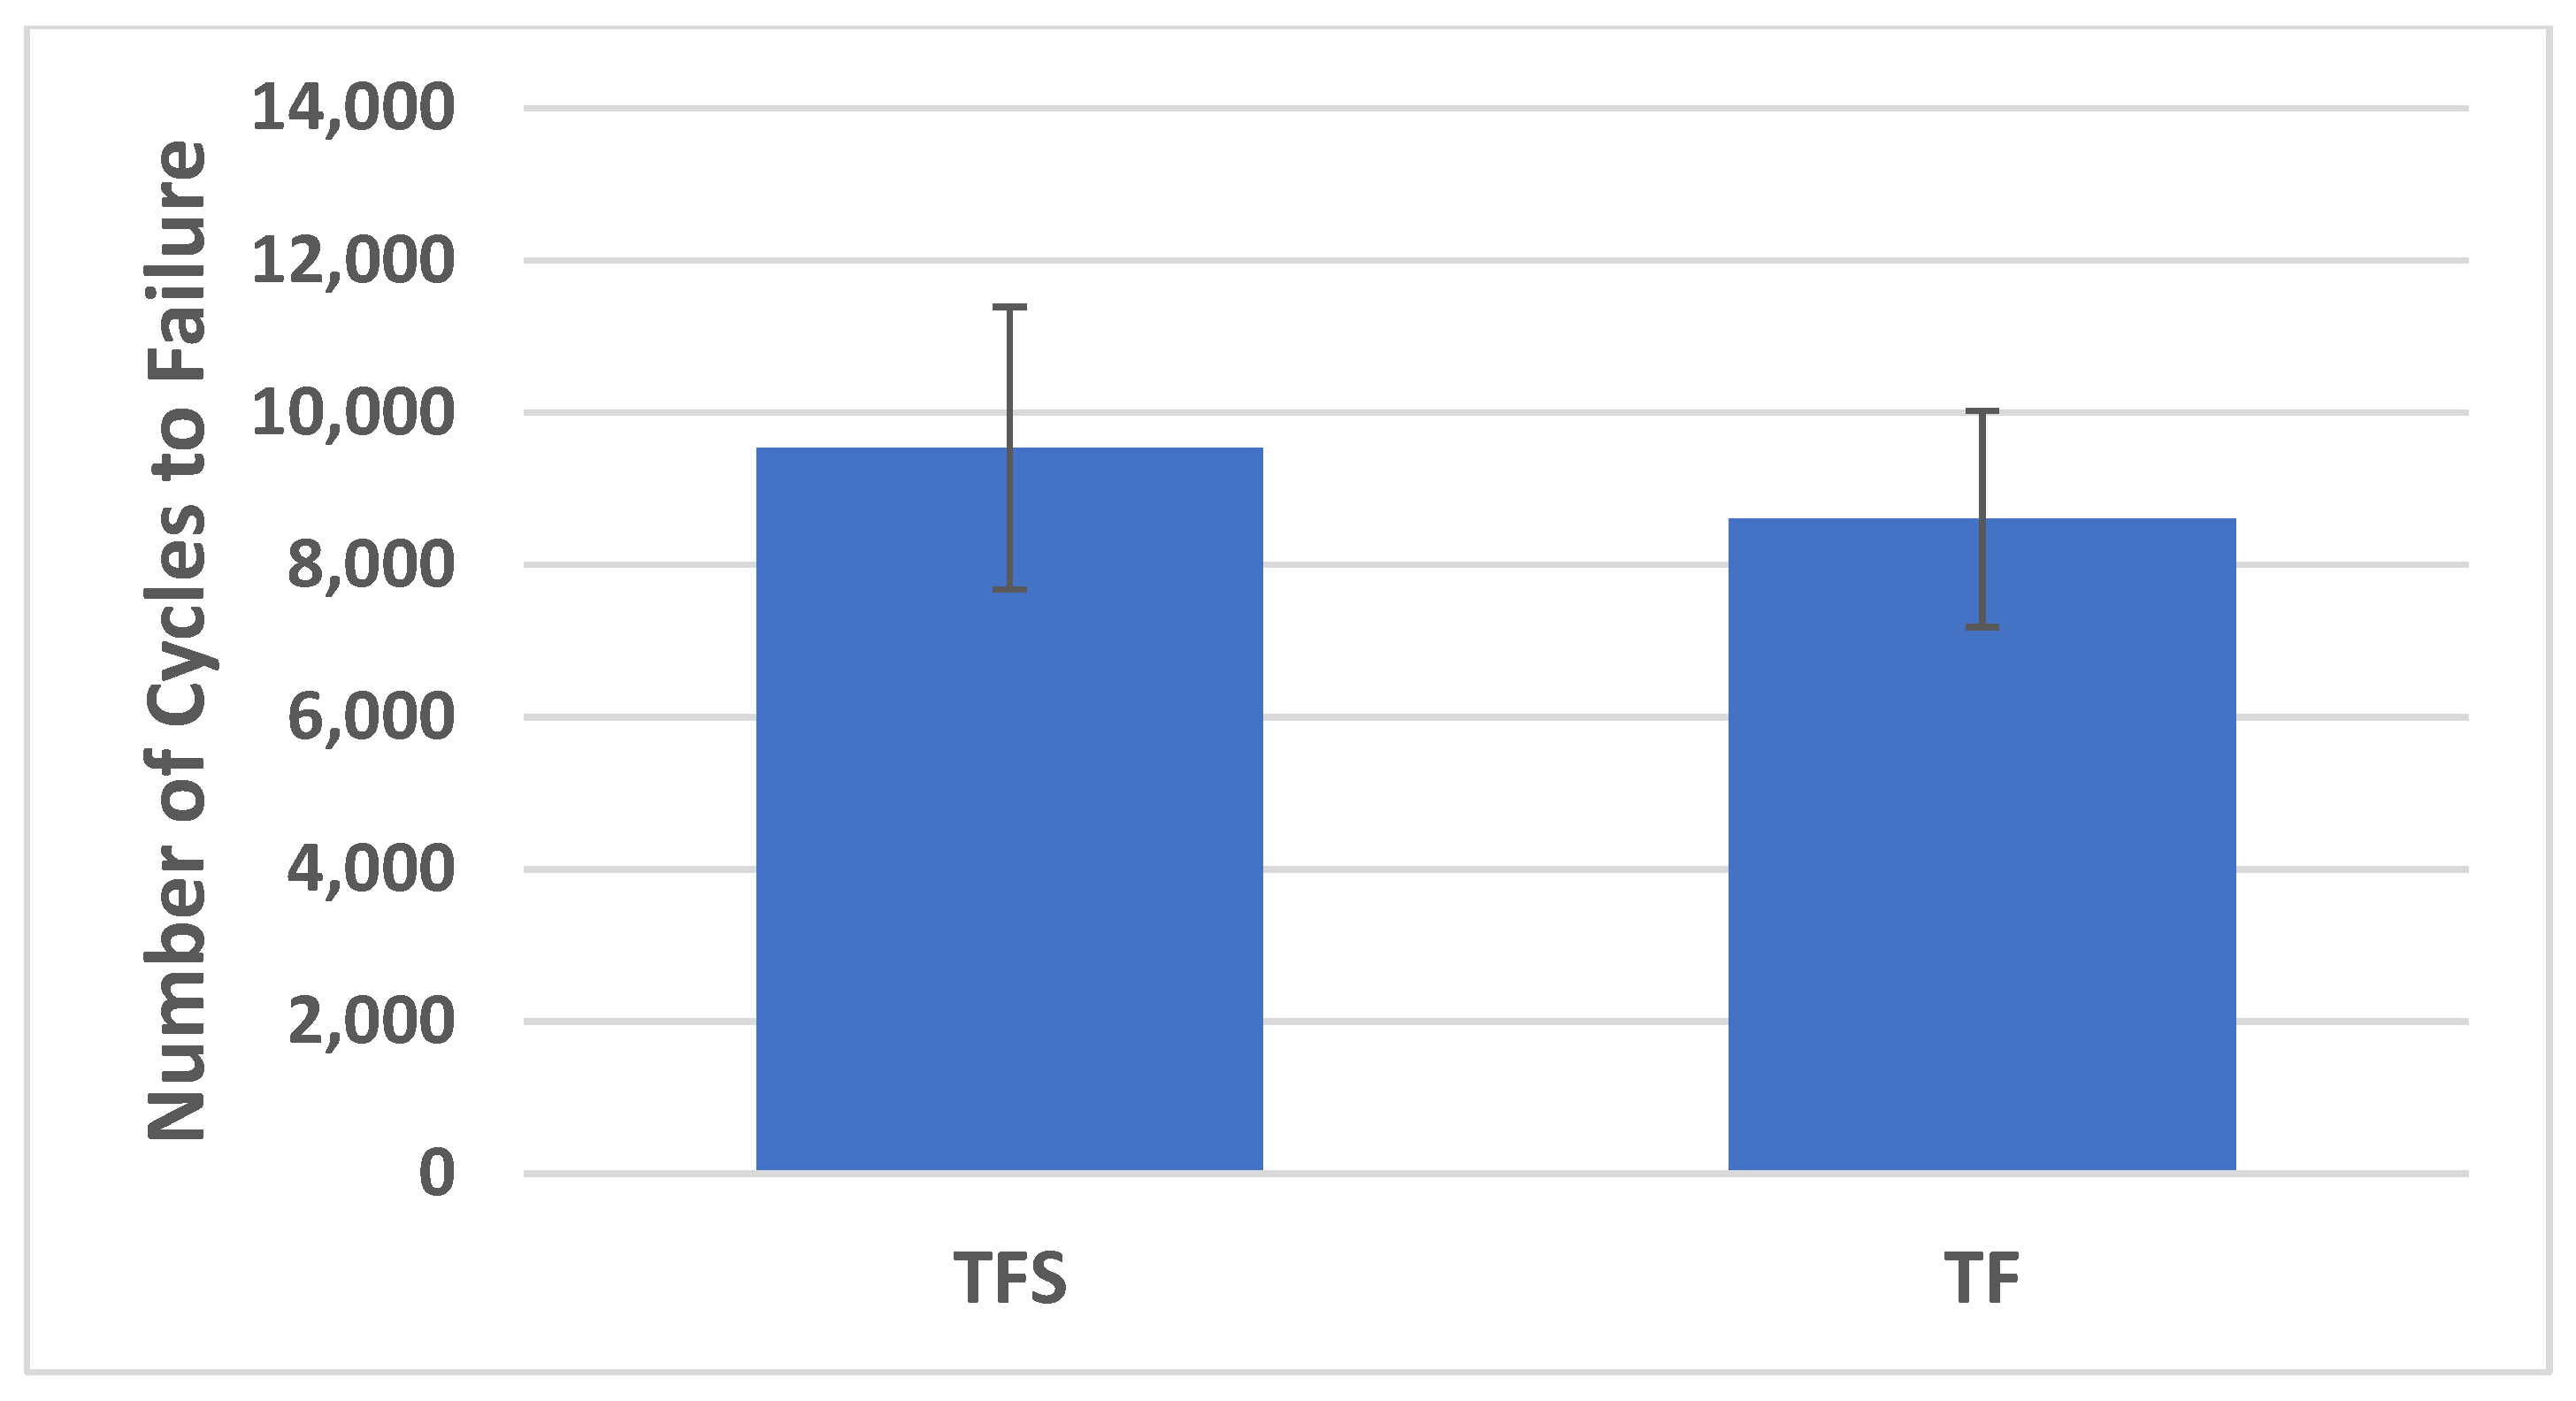

3.3. Cycles to Failure